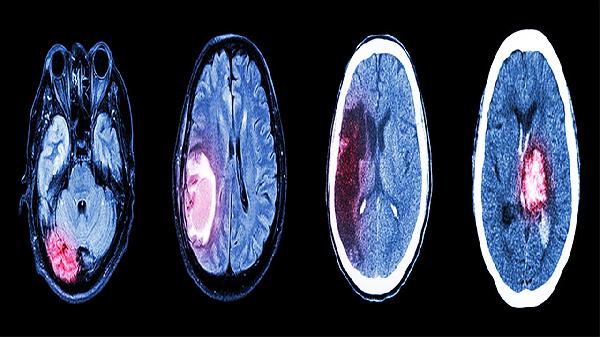

闭合性颅脑损伤轻型患者通常症状较轻,意识障碍持续时间较短,一般在数分钟至数小时内恢复。头痛多为轻度至中度,可通过休息缓解。头晕可能伴随恶心,但呕吐较少见。部分患者可能出现短暂记忆力减退,但对日常生活影响较小。神经系统检查通常无阳性体征,影像学检查如头颅CT或MRI多数无明显异常。这类损伤通常无须特殊治疗,以观察和休息为主。症状一般在1-2周内逐渐消失,不会遗留长期后遗症。

少数闭合性颅脑损伤轻型患者可能出现症状加重或持续时间延长的情况。若头痛持续不缓解或逐渐加重,出现频繁呕吐、意识状态改变、肢体无力等症状,需警惕颅内出血或脑水肿的可能。部分患者可能发展为脑震荡后综合征,表现为持续头痛、头晕、注意力不集中等症状。老年人、儿童及有基础疾病的患者恢复可能较慢。出现上述情况时需及时就医,完善相关检查并接受针对性治疗。